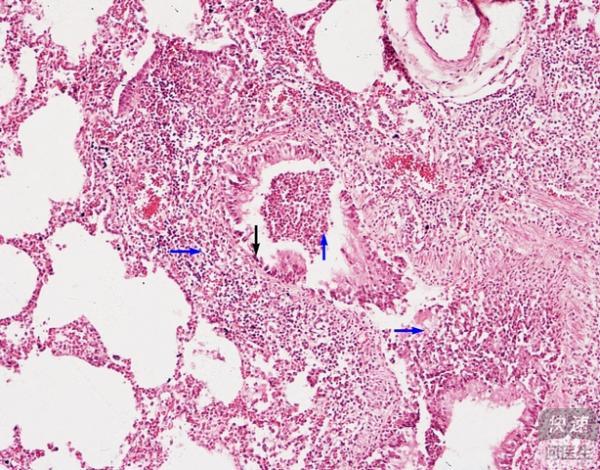

小叶性肺炎显微图片20张

小叶性肺炎病理图

小叶性肺炎镜下图

小叶性肺炎图片标注

小叶性肺炎病理切片图

小叶性肺炎镜下观图片

小叶性肺炎病理切片